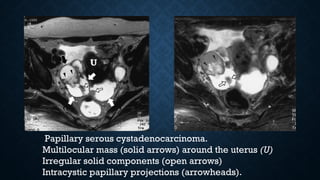

Papillary serous cystadenocarcinoma.

Multilocular mass (solid arrows) around the uterus (U)

Irregular solid components (open arrows)

Intracystic papillary projections (arrowheads).

Papillary serous cystadenocarcinoma. Multilocularmass (solid arrows) around the uterus (U) Irregular solid components (open arrows) Intracystic papillary projections (arrowheads).